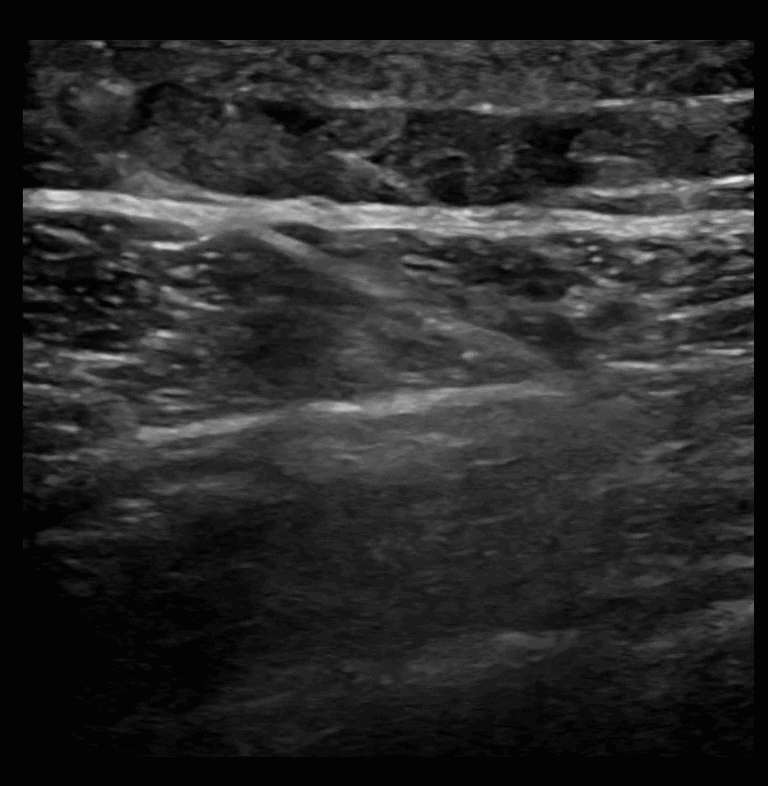

SAPB 2: The latissimus dorsi muscle sits superficial to the serratus anterior muscle. A color box on the latissimus dorsi muscle identifies vasculature.

SAPB 3: Needle is guided in long axis from posterior to anterior with the target being the fascial plane that separates the latissimus dorsi muscle from the serratus anterior muscle.